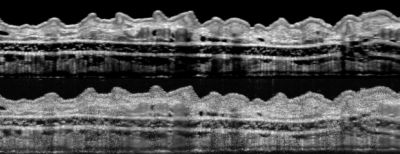

Now, averaging the successive images removed the speckles. The research team used the resulting enhanced capability to acquire detailed, essentially noise-free images of a living, anesthetized mouse's ear, including sebaceous glands, hair follicles, blood vessels, and lymph vessels, Liba says.